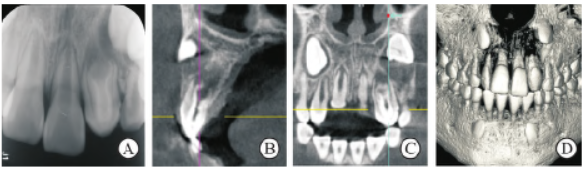

影像学检查:根尖片及锥形束CT(CBCT)示22 冠部硬组织内陷超过釉牙骨质界达根尖,牙根发育Nolla 8 期,根尖孔呈喇叭口状,根尖周大范围低密度影像,边界不清;23 牙胚周围硬骨板不完整,牙胚唇向扭转;12 根管形态正常,牙根发育Nolla 9期,根尖周无异常(图2)。